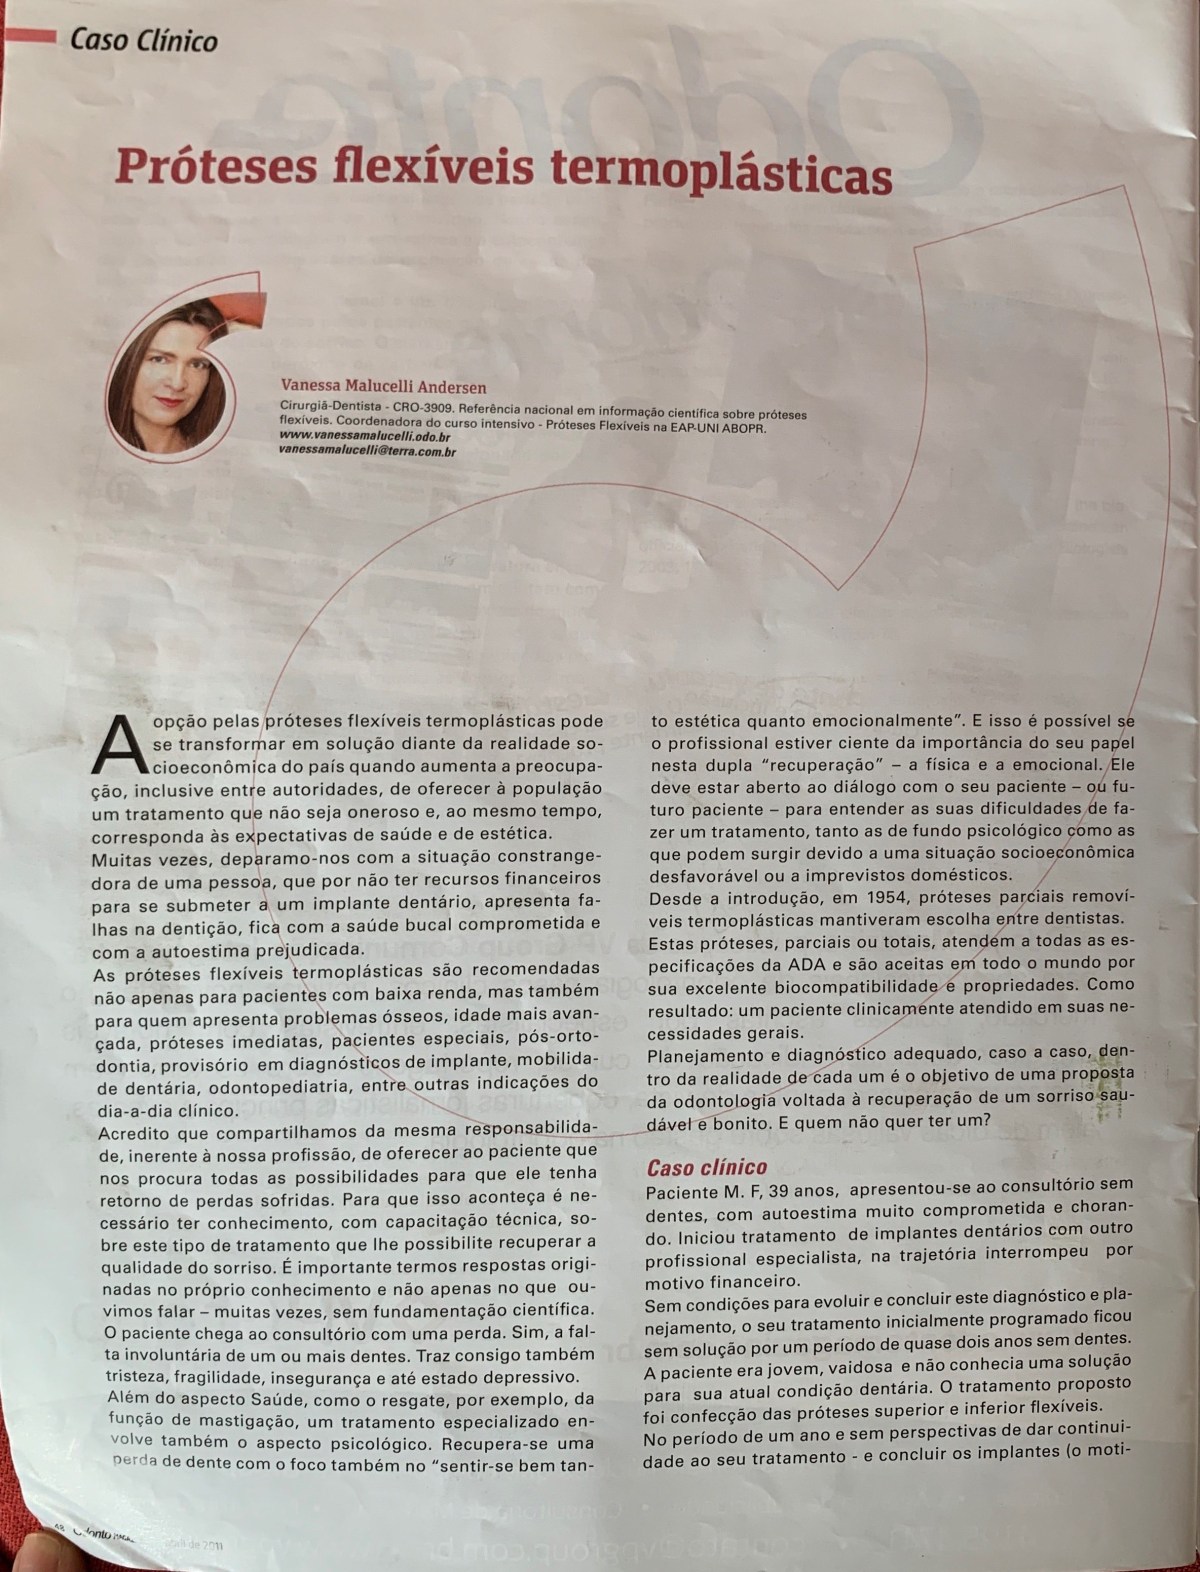

Próteses Flexíveis Termoplásticas

SLIDE PRINCIPAL(COM POLIMEROS)Saude_Bucal_Ctba-CPODPALESTRA 2009 – cópiaSLIDE TONALIDADESHERMÍNIO HOMMETOSLIDE INJETORA TERMOPLÁSTICACURSO…